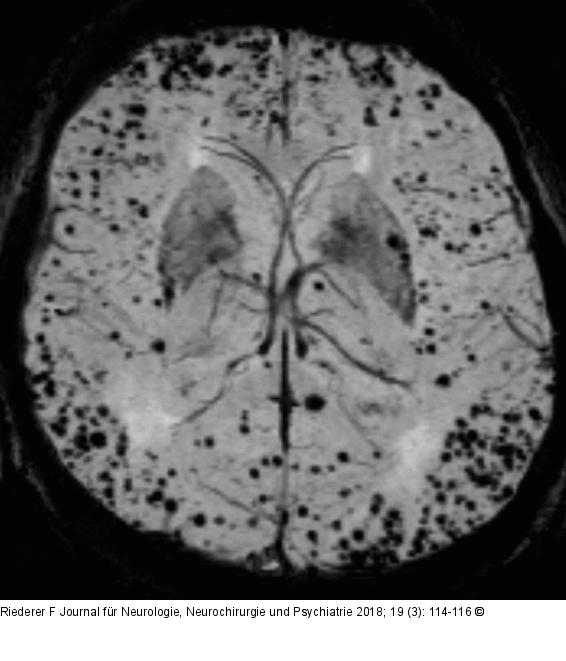

Abbildung 1: Signalauslöschungen Signalauslöschungen durch Hämosiderinablagerungen durch zerebrale Mikroblutungen dargestellt durch eine Suszeptilitätsgewichtete Sequenz (SWI) |

Signalauslöschungen durch Hämosiderinablagerungen durch zerebrale Mikroblutungen dargestellt durch eine Suszeptilitätsgewichtete Sequenz (SWI) |